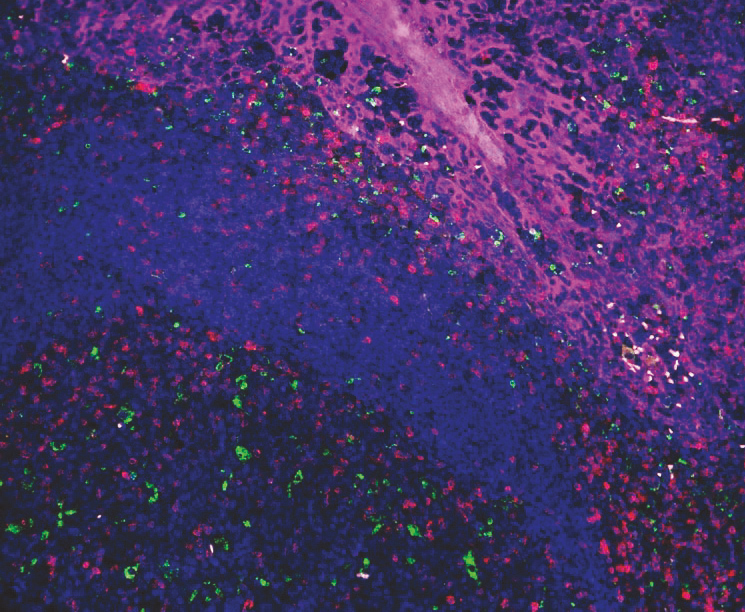

| ☝上图为:使用VectaPlex™进行六轮染色后的合成图像。 |

| 样本为胃FFPE: 6种小鼠来源的一抗,分别为CD20 (红色), CD34 (黄色), Desmin (青色), AE1/AE3 (品红), CD3 (灰色), Vimenn (绿色) ,二抗为horse anti-mouse IgG DyLight™ 488。蓝色为DAPI染色。使用Vector® TrueView® 试剂盒用于去除组织自发荧光。 |